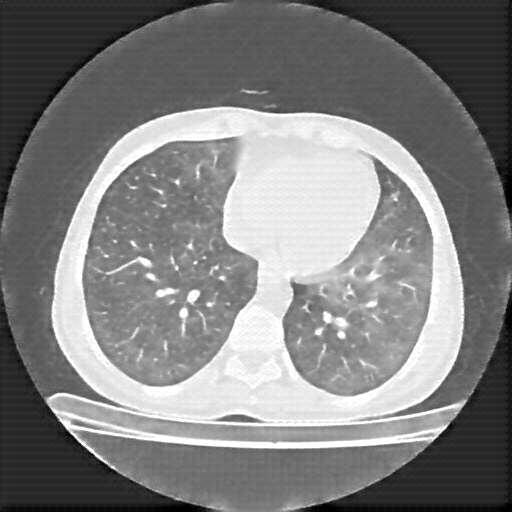

Original NATIVE CT scan (input)

Lung window (WL -600, WW 1500 β†’ Low βˆ’1350, High +150)

Reconstructed NATIVE CT scan (cycle consistency)

Original VENOUS CT scan

Generated VENOUS CT scan (A→B translation)